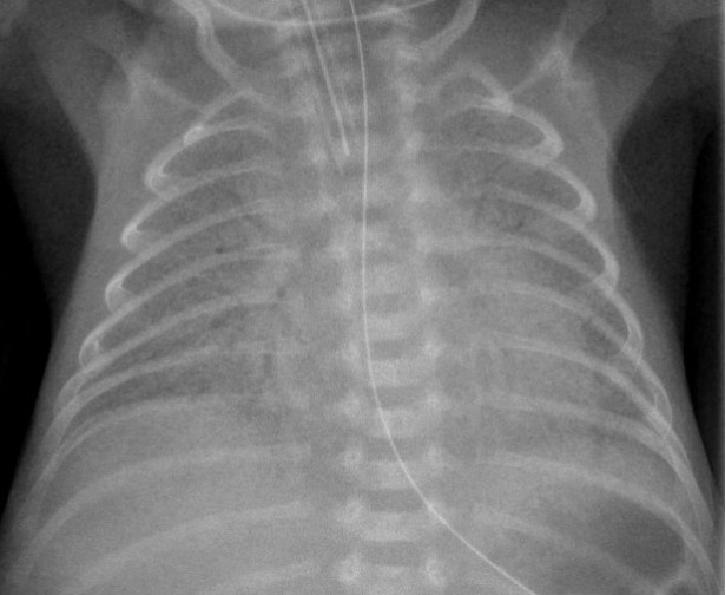

1、28周早产儿,呼吸困难1天。

可见双侧对称弥漫分布的的颗粒状高密度影。可见支气管充气。

这就是典型的新生儿特发性呼吸窘迫综合征(RDS)。

其特征性 X 线表现为:

1)两肺野透光度普遍减低,呈毛玻璃状,或两肺野中内带多发细小颗粒状或小结节和网状影,下肺野较上肺野更为显著;

2)气管支气管充气显著,在两肺野密度普遍性增加的对比之下显示更为清楚;

3)胸廓扩张良好,横膈位置正常。 对怀疑本病者,短期(1 ~ 2h)连续拍片观察,对诊断意义较大;有文献提出凡 6~ 12h 胸部影像尚无确切网粒阴影者,可排除本病。